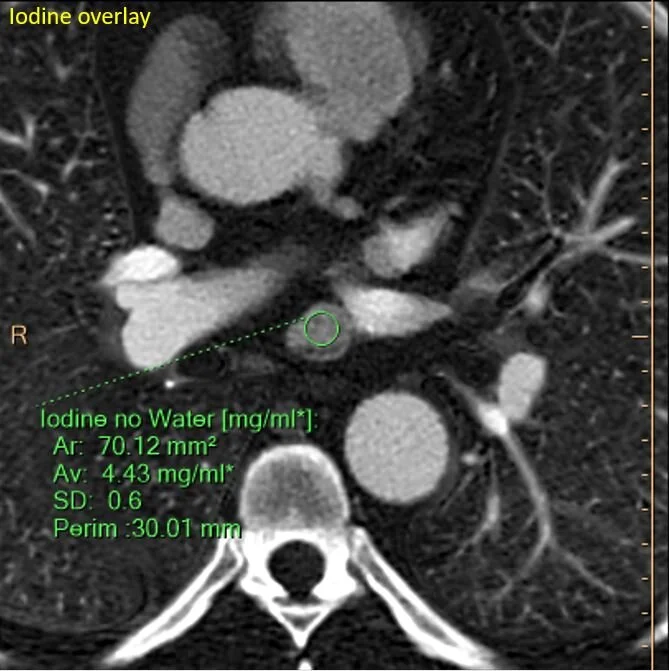

The subcarinal nodule has intense uptake on iodine map.

Quantitatively intense iodine uptake.